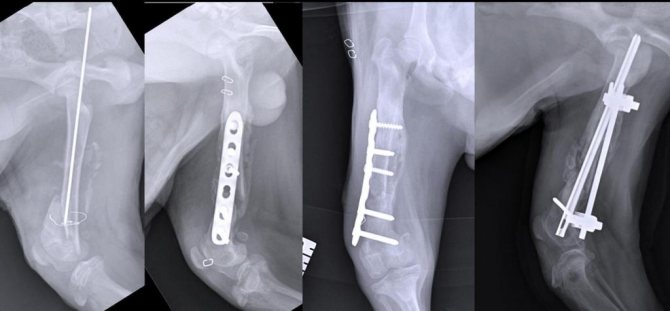

Суть его заключается в том, что в процессе операции обломки костей сопоставляются друг с другом с помощью различных фиксаторов. Как правило, это специальные винты, штифты, шурупы, проволоки, спицы или гвозди, сделанные из стойких к постоянному механическому воздействию неокисляющихся материалов.

Для подобных имплантатов используют костную ткань, инертные пластиковые фиксаторы и такие вещества, как титан, нержавеющая сталь, кобальтовый сплав виталлиум.

- Наружный, или чрескостный, при котором для соединения костных обломков снаружи используется аппарат Илизарова и другие аналогичные устройства.

- Внутренний, или погружной, когда кости фиксируются имплантатами внутри тела пациента. Во время оперативного вмешательства используют один из видов анестезии. После накостного погружного остеосинтеза кости зачастую дополнительно фиксируют наложением гипсовой повязки.

Остеосинтез применяется для сопоставления отломков длинных трубчатых костей голени, бедра, плеча и предплечья, а также при внутрисуставных переломах и для сращивания поврежденных мелких костей стопы и кисти.

Благодаря произведенной при остеосинтезе фиксации достигается неподвижность сломанных костей, что позволяет им срастаться физиологически правильно.

Это очень популярный способ лечения переломов, которые срослись неправильно. Суть этой операции заключается в том, что фрагменты поломанной кости прикрепляют один к другому, используя различные фиксаторы. Они могут быть в виде специальных шурупов, винтов, спиц и т. п. Фиксаторы делаются из крепкого неокисляющегося материала, это может быть костная ткань, специальный пластик, нержавеющая сталь, титан и другие материалы.

Имплантаты используются долгое время, что позволяет кости в месте перелома полностью восстановиться.

Остеосинтез может быть двух видов:

- Наружный, его еще называют чрескостным. Во время такой операции соединяются костные обломки. Снаружи все закрепляется с помощью аппарата Илизарова или других похожих устройств.

- Внутренний (погружной). Этот метод отличается от предыдущего тем, что имплантаты закрепляют кости внутри тела, а не снаружи. После этой операции часто проводится дополнительная фиксация с помощью гипсовой повязки.

Остеосинтез обычно применяется в случаях, когда необходимо соединить длинные трубчатые кости ног (бедро, голень) и рук (плечо, предплечье), а также при переломах суставов и мелких костей кисти и стопы.

Фиксация при остеосинтезе сохраняет сломанные кости в неподвижном состоянии, и поэтому они срастаются правильно.